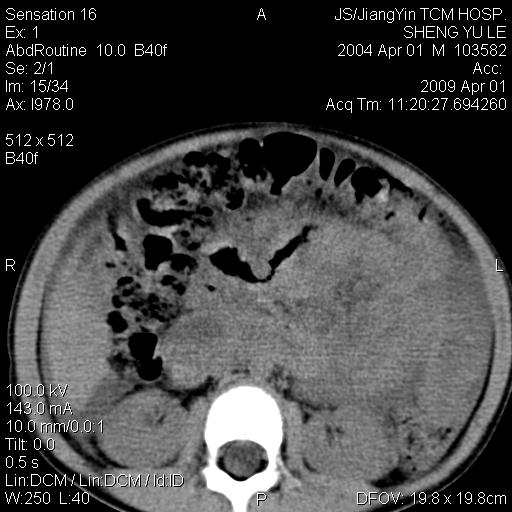

m,5岁。尿痛尿频数天。既往无病史。ct平扫腹盆腔积液。膀胱壁明显增厚。另可见心包增厚。wbc5万,骨髓穿等结果。请指教。

膀胱影像表现结合临床应该是急性膀胱炎症,但为什么有腹水呢?双肾输尿管无扩张,泌尿系压力应该不大不至于引起尿外渗,应该是腹膜感染引起的,但楼主没有提及相关症状,腹膜及膀胱结核?患者白细胞5万(结核不至于这么高啊),脾脏增大,是不是有白血病?进一步检查。。

腹水,膀胱壁增厚,wbc5万,结合临床,支持感染性疾病---感染性腹膜炎、腹水,急性膀胱炎,败血症。期待结果。